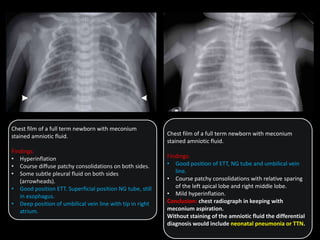

Chest film of a full term newborn with meconium

stained amniotic fluid.

Findings:

• Hyperinflation

• Course diffuse patchy consolidations on both sides.

• Some subtle pleural fluid on both sides

(arrowheads).

• Good position ETT. Superficial position NG tube, still

in esophagus.

• Deep position of umbilical vein line with tip in right

atrium.

• Good position of ETT, NG tube and umbilical vein

line.

• Course patchy consolidations with relative sparing

of the left apical lobe and right middle lobe.

• Mild hyperinflation.

Conclusion: chest radiograph in keeping with

meconium aspiration.

Without staining of the amniotic fluid the differential

diagnosis would include neonatal pneumonia or TTN.